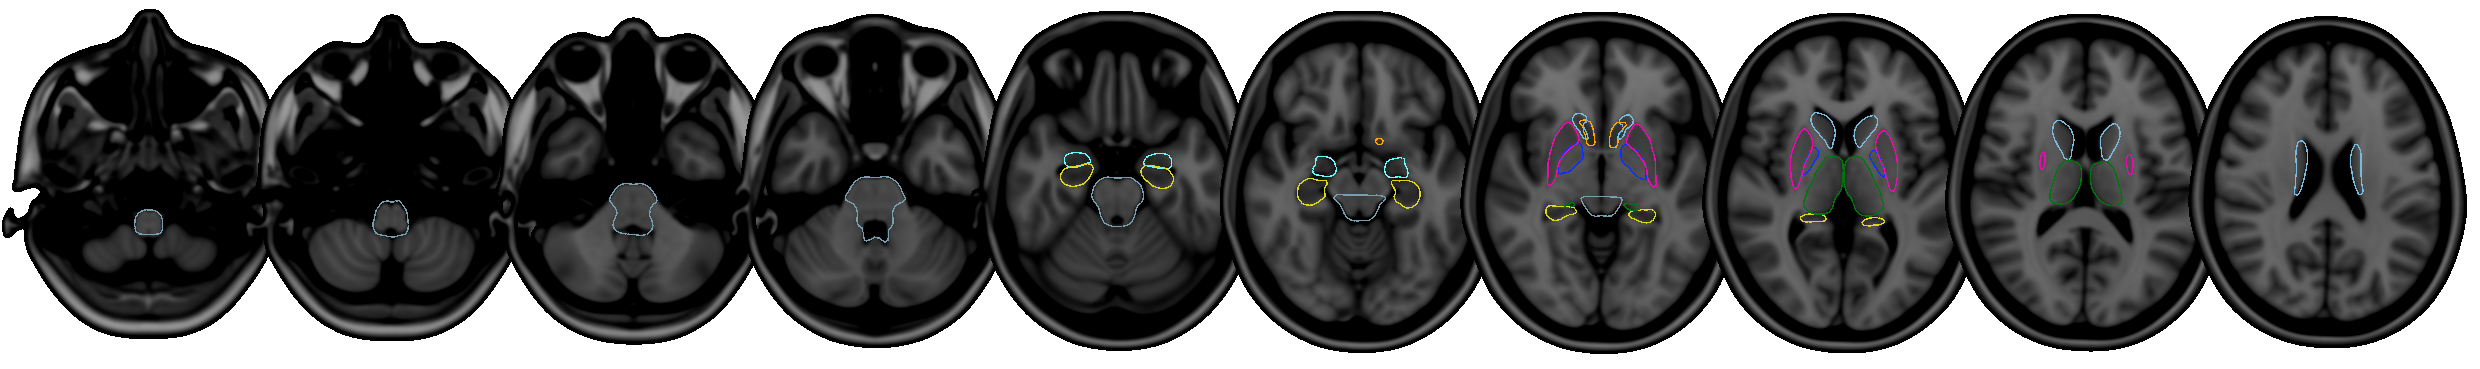

FIRST is a model-based segmentation/registration for automatic segmentation of a number of subcortical structures.

The supported structures are listed below. To segment these structures, FIRST needs a good quality T1-weighted image:

- Putamen (

Puta) - Caudate nucleus (

Caud) - Nucleus accumbens (

Accu) - Globus pallidus (

Pall) - Hippocampus (

Hipp) - Amygdala (

Amyg) - Thalamus (

Thal) - Brainstem (

BrStem)

The shape/appearance models used in FIRST are constructed from manually segmented images provided by the Center for Morphometric Analysis (CMA), MGH, Boston. The manual labels are parameterized as surface meshes and modelled as a point distribution model. Deformable surfaces are used to automatically parameterize the volumetric labels in terms of meshes; the deformable surfaces are constrained to preserve vertex correspondence across the training data. Furthermore, normalized intensities along the surface normals are sampled and modelled. The shape and appearance model is based on multivariate Gaussian assumptions. Shape is then expressed as a mean with modes of variation (principal components). Based on our learned models, FIRST searches through linear combinations of shape modes of variation for the most probable shape instance given the observed intensities in a T1-weighted image.

Supported structures

The structures that FIRST can segment are listed below. The Abbrevbiated name column gives the name that you should pass to the FIRST command-line tools when you want to segment a specific structure. The Integer label column gives the integer label that FIRST assigns to each structure in its output files (e.g. output_*_firstseg.nii.gz). The Modes column gives the recommended number of modes of variation to use for each structure when fitting the subcortical model (note that this is normally taken care of automatically for you).

| Structure | Abbreviated name | Integer label | Modes |